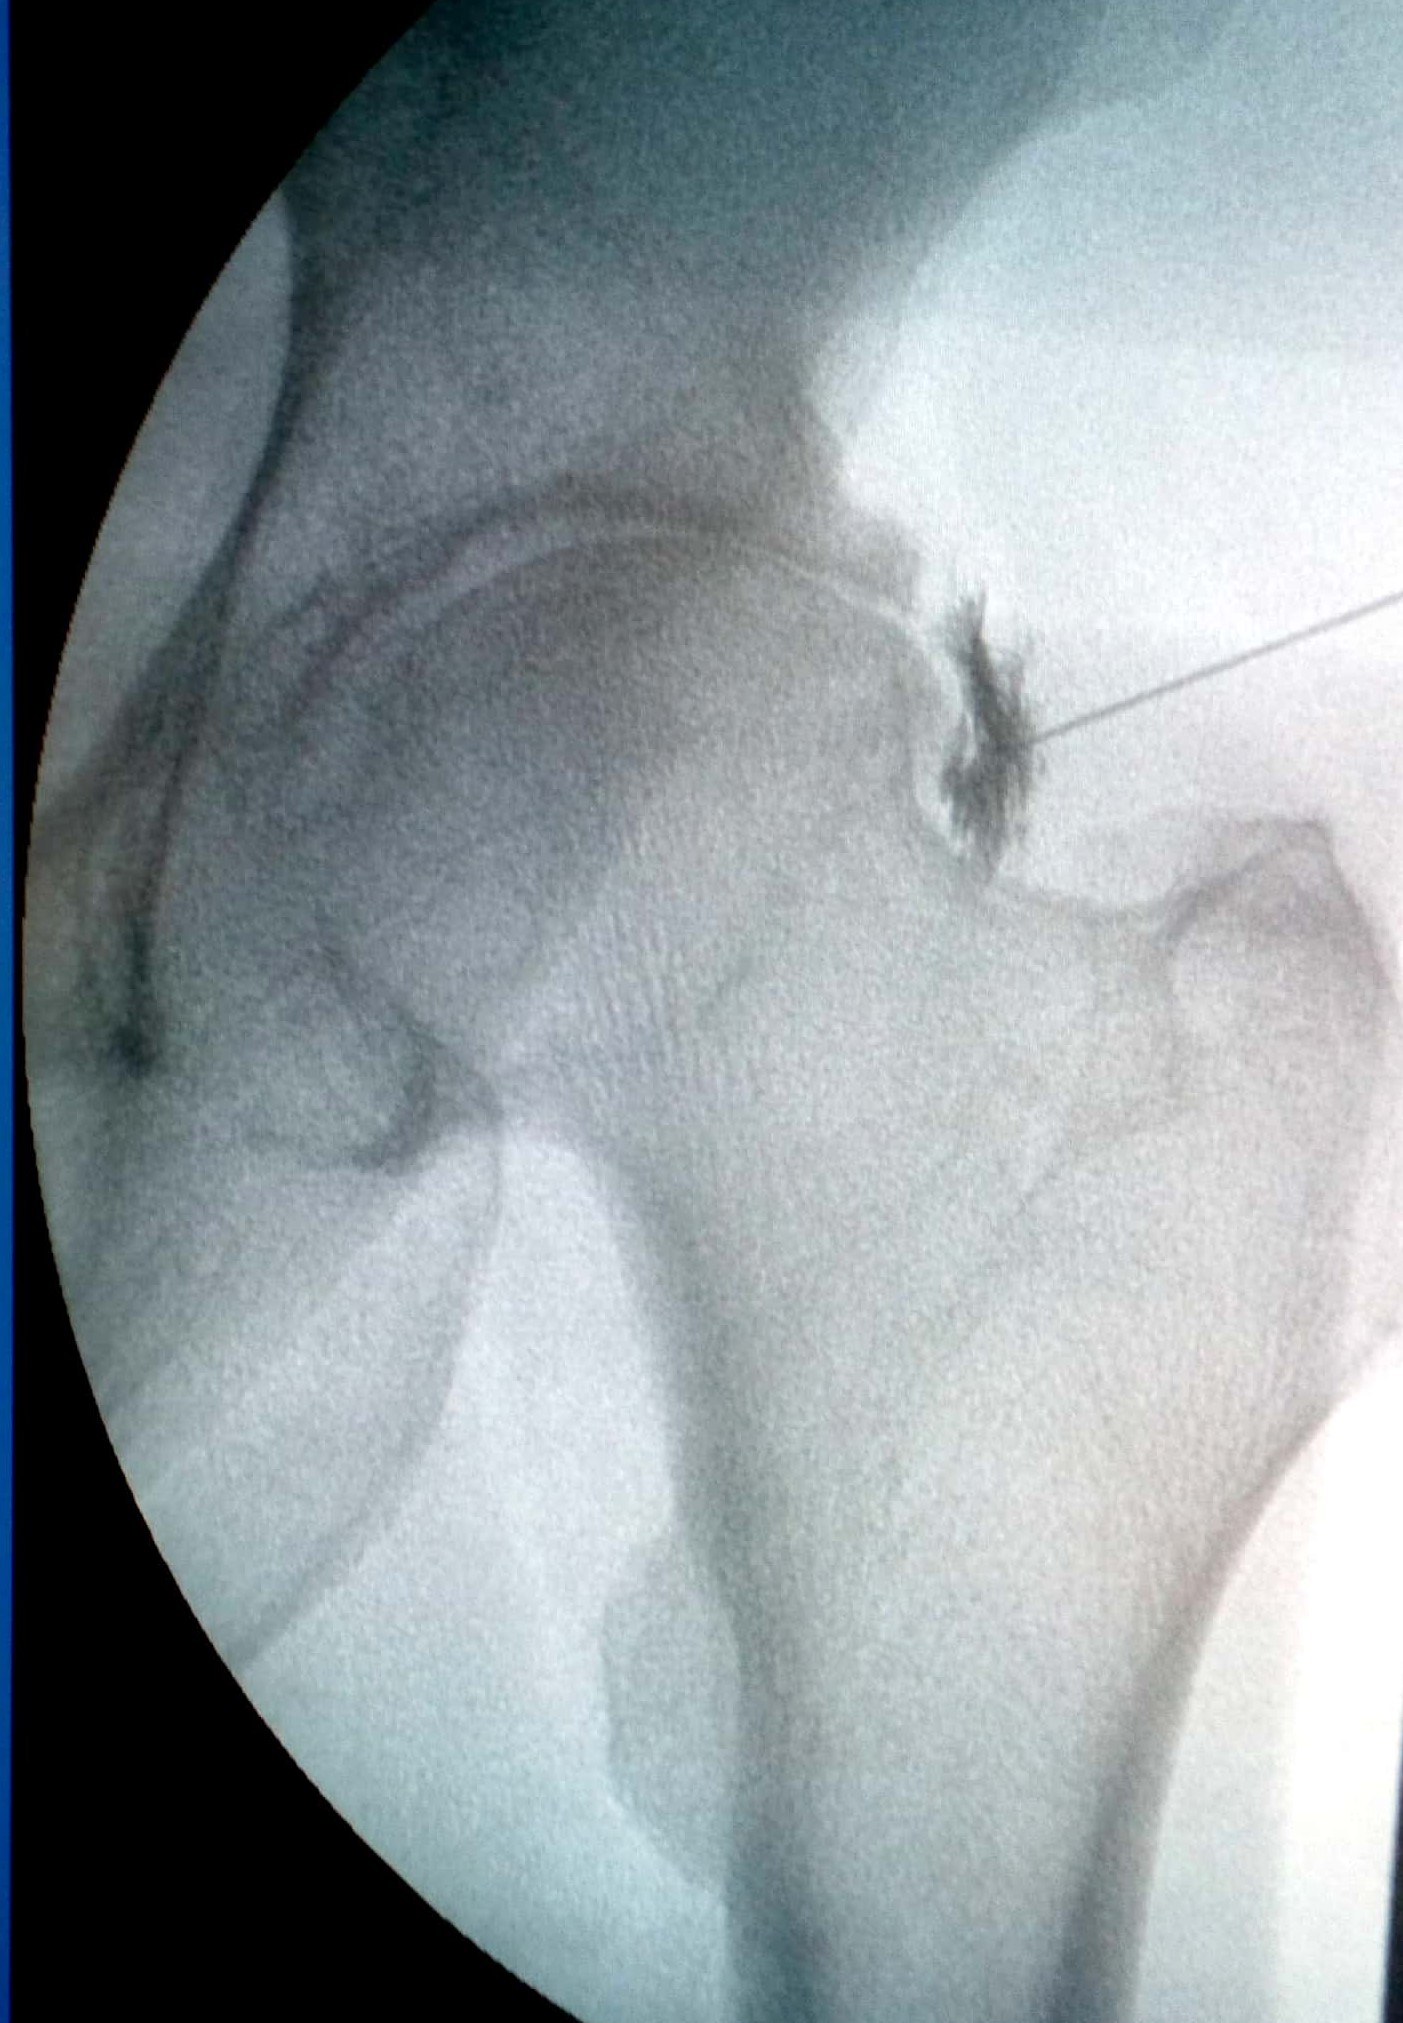

Ασθενής με οστικό οίδημα ισχίου

Ασθενής 67 ετών, με άλγος δεξιού ισχίου. Η μαγνητική έδειξε ότι υπάρχει οστεοαρθρίτιδα με οστικό οίδημα. Πραγματoποιήθηκε έγχυση ισχίου με υαλουρονικό και τοπικό αναισθητικό. Ο ασθενής ένιωσε άμεσα ανακούφιση που διατηρείται έως σήμερα 1.5 χρόνο μετά